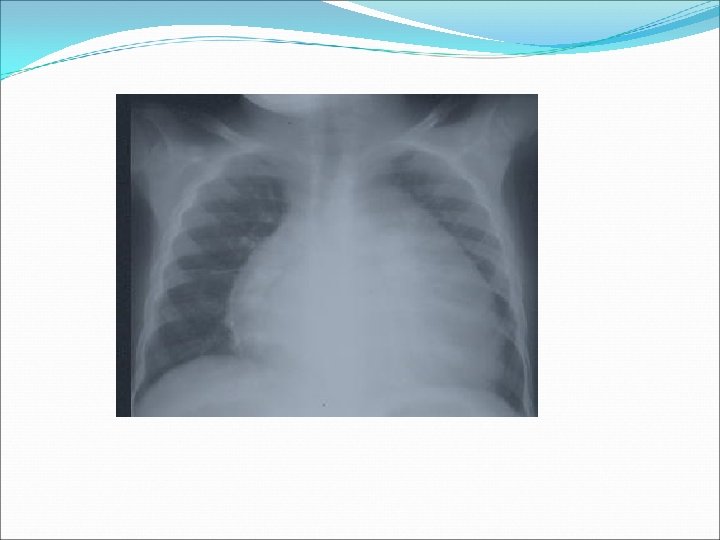

�Telekardiyografide kardiyomegali mevcuttur. �Telekardiyografide kardiyomegali yoksa, KKY tanısı neredeyse ekarte edilebilir. �Ayrıca akciğer alanlarında konjesyon bulguları gözlenir. Perivasküler ve peribronşiyal fazla miktarda sıvı toplanmasına bağlı olarak perihiler bölgede kelebek şeklinde puslu opasiteler görülebilir. �

�Telekardiyografide interstisyel ödeme bağlı olarak Kerley A (hilustan yukarı doğru uzanan ince lineer çigiler) ve Kerley B (akciğerin periferinde kostofrenik açıya yakın horizontal linner densiteler) çizgileri izlenir.